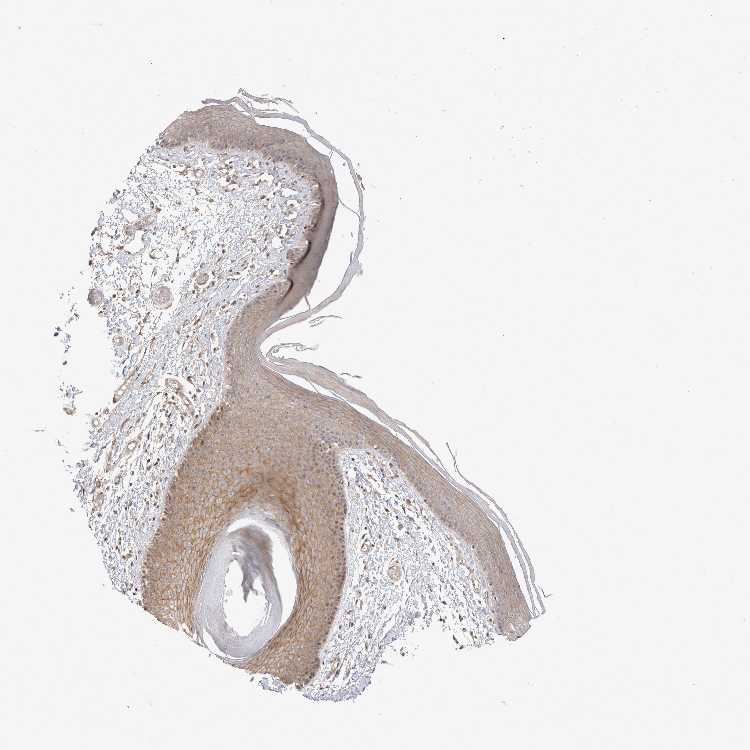

SKIN 1 - Antibody stainingi

Antibody staining in the annotated cell types in the current human tissue is reported as not detected, low, medium, or high, based on conventional immunohistochemistry profiling in selected tissues. This score is based on the combination of the staining intensity and fraction of stained cells.

Each image is clickable and will lead to virtual microscopy that enables deeper exploration of all samples and also displays staining intensity scores, fraction scores and subcellular localization as well as patient and tissue information for each sample.

Antibody HPA025958Antibody CAB020722

Langerhans MediumLow

Fibroblasts MediumMedium

Keratinocytes MediumLow

Melanocytes MediumLow